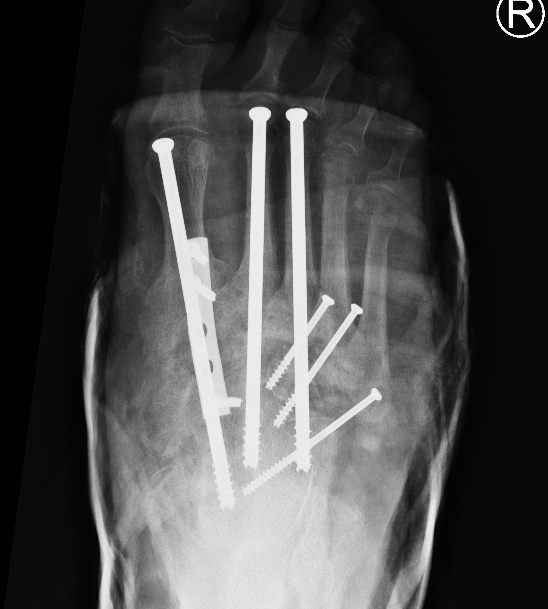

Midfoot Osteotomy and Arthrodesis

Options

Plates

Intramedullary screws

Technique

Superconstructs (4 concepts)

1. Fusion is extended beyond the zone of injury to bridge the area of bony dissolution

2. Aggressive bone resection - allows reduction of deformity with reduced soft tissue tension

3. Stronger implants - medial / central and lateral column fixation

4. Load sharing devices

- intramedullary beams

- axial screw fixation from 1st MTPJ through metatarsal into talus

- also IM screw through 2nd and 3rd metatarsal into talus